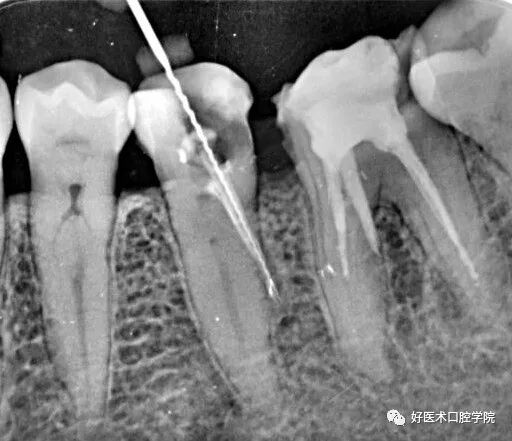

超充问题:

牙胶尖什么颜色早读 | 几十年牙医总结临床经验,现在只需几分钟便可全部了解!_https://www.jmylbn.com_新闻资讯_第22张

工作中有很多根管治疗后的牙齿出现超充的现象,患者出现胀痛咬合痛。究其原因:

1. 医生根管预备过程中主尖挫和扩大针选择和使用不当突破了根尖狭窄部位。

2. 根管预备后牙胶尖主尖选择不当。

3. 试尖后没用X线确定。

4. 确定根管长度后选择第一个辅尖过细,侧方加压时用力过大引起超充。

5. 根管测量仪使用不当,根管预备到红色警戒线区,这时根尖狭窄部完全破坏成开放状。

主要原因就是根管狭窄部被破坏,这时再测量各根管长度无任何意义,测量的长度已经是超充后的长度了。其实只要不破坏狭窄部想超充都很难,因为牙胶尖比较软尖端一碰到狭窄部就弯曲了,除非你选用20号以下的牙胶尖做主尖了。